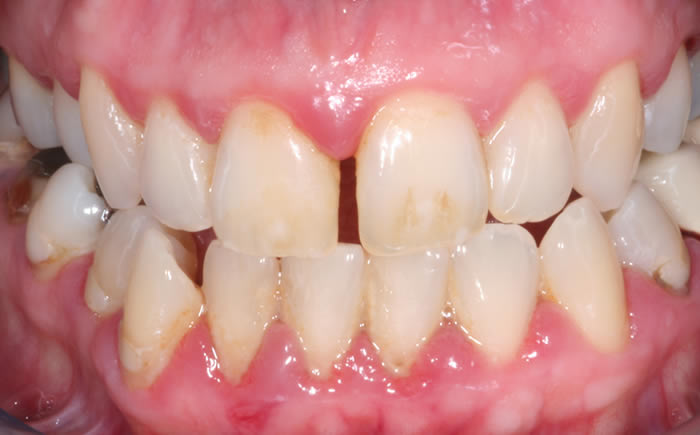

Full arches of teeth replaced by dental implants

Case One (5 images)

Full set of lower teeth fixed onto five dental implants.